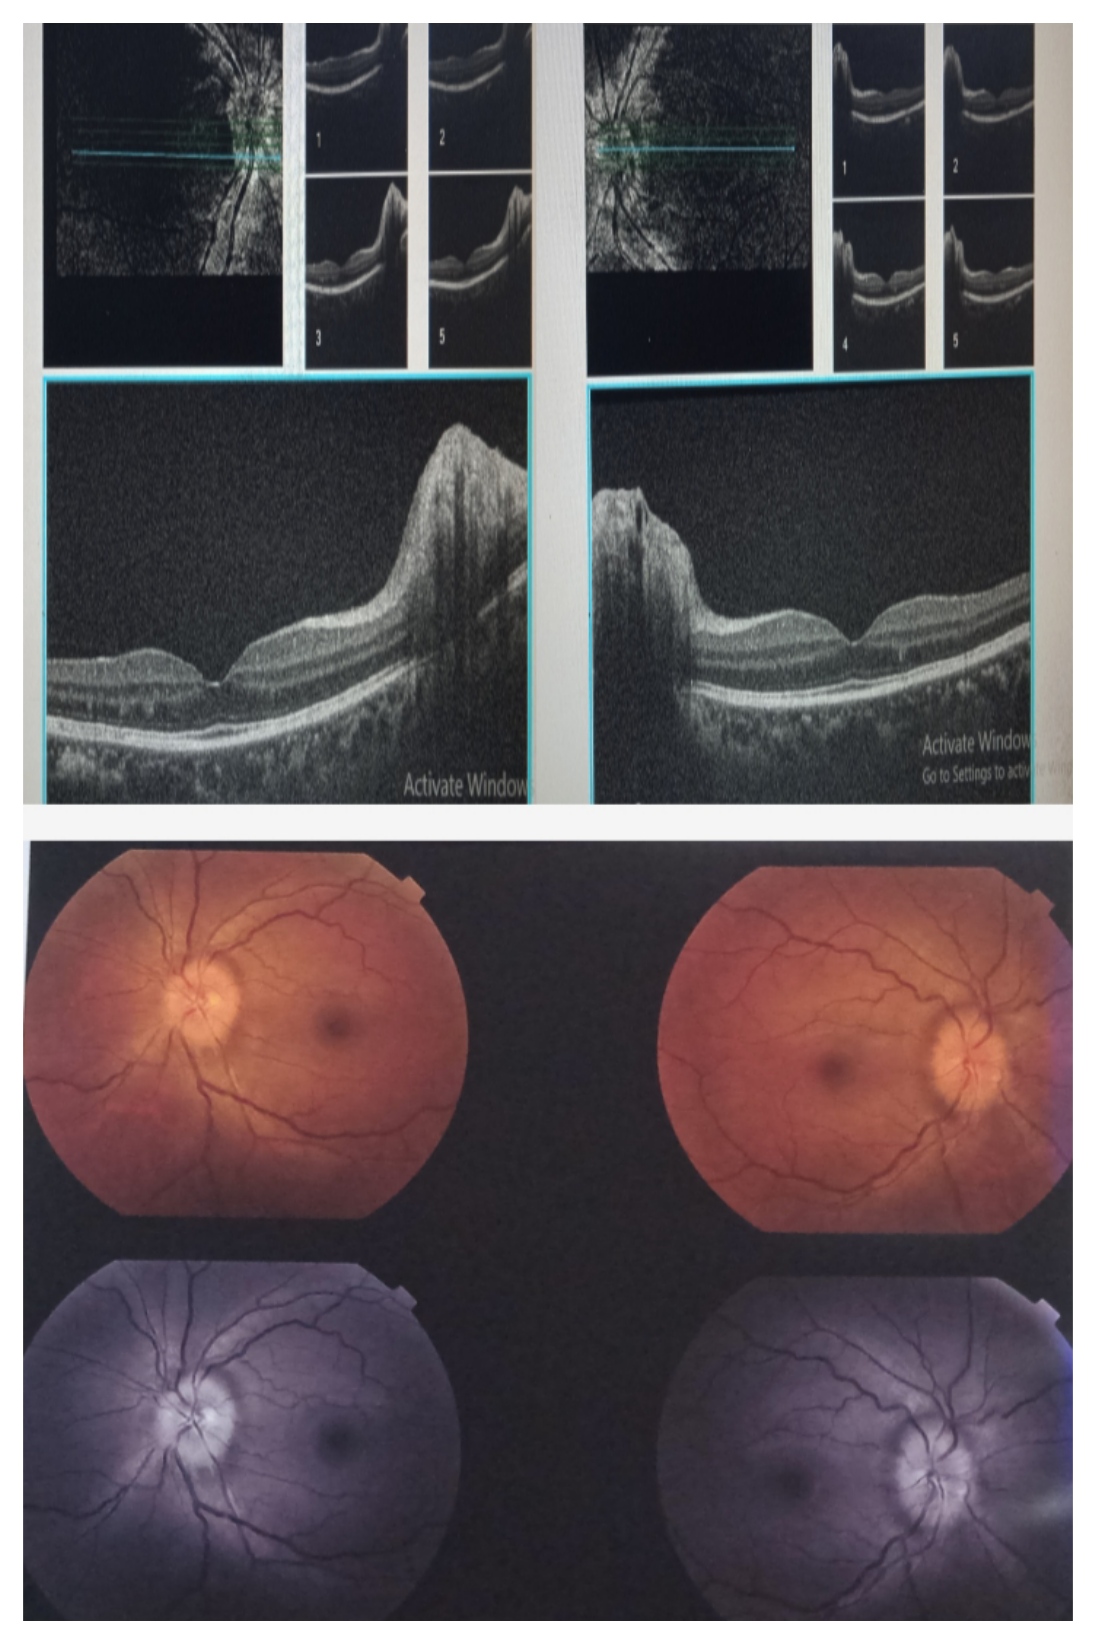

उम्र 16 वर्ष

शिकायत . फटाखे द्वारा चोट लगने से दिखने लगा कम

प्राथमिक जांच में मोतियाबिंद पाया गया साथ ही कार्निया भी क्षतिगृस्त हुआ जिनका समय रहते आपरेशन किया गया ,लेकिन नजर में ज्यादा परिवर्तन नहीं आया ,अन्य जांच OCT किया गया जिस जांच मे देखा गया की पर्दे में छेद हो चुका है।